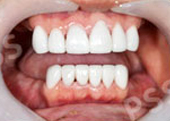

Case from Phuket Dental Crowns & Bridge

teeth crowns bridges

crown bridges

teeth bridges

tooth crown